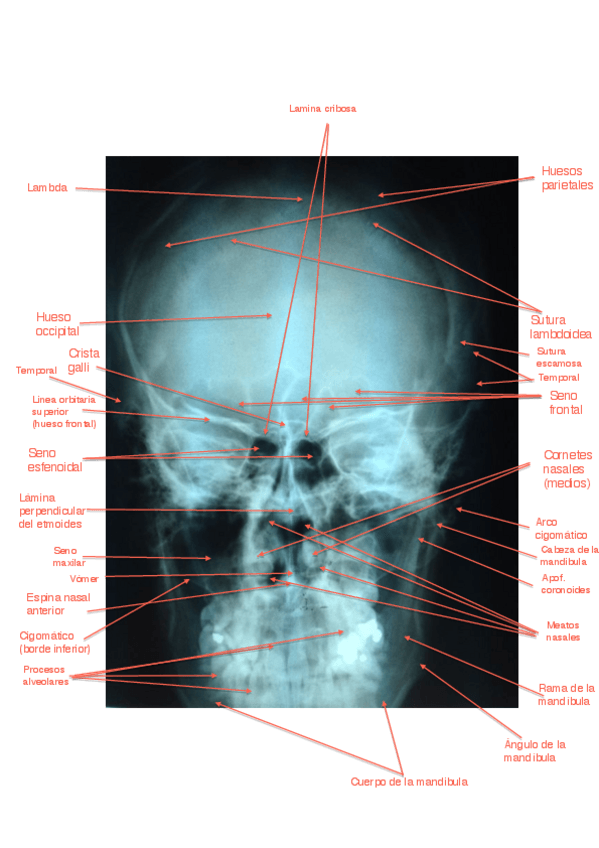

Radiografías del cráneo con anotaciones para el examen PRAC

6 páginas